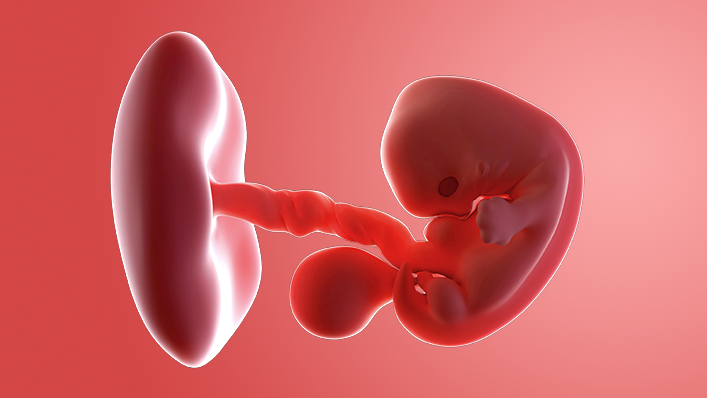

Your baby is now around 16mm long, which is about the size of a raspberry. By next week, they will be twice the size!

The tiny head has started to uncurl a bit. Their arms are getting longer and are bigger than the legs as the upper part of the body grows faster than the lower part. The legs are getting longer too, although the knees, ankles, thighs and toes have not developed yet.

Around now, your embryo becomes a "foetus", which means offspring in Latin.